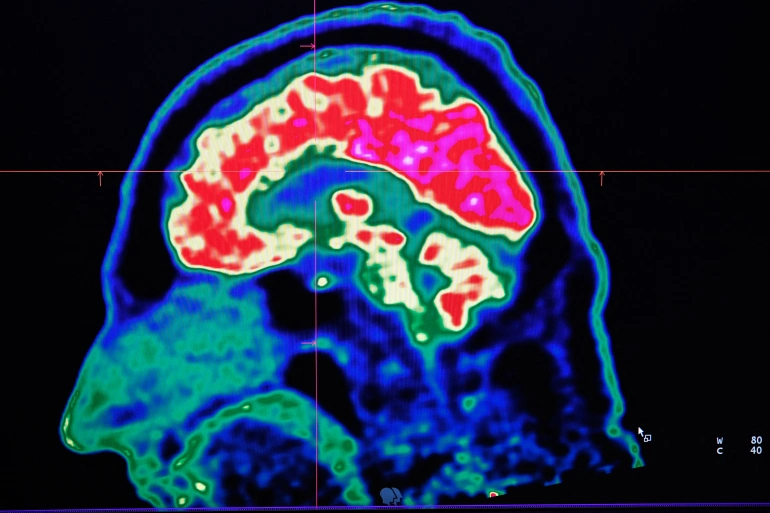

ويقول الكاتب نيك موردوفانيك في هذا التقرير الذي نشرته مجلة “نيوزويك” (Newsweek) الأميركية إن هذه الدراسة-التي تم نشرها في دورية “أنالز أوف نيورولوجي” (Annals of Neurology)- بحثت في انتشار ظاهرة إزالة الاستقطاب في القشرة المخية البشرية، وقدمت فهما جديدا حول تفاعل الدماغ مع نضوب الطاقة.

يمكن تشبيه عملية إزالة الاستقطاب (Depolarization) من خلايا الدماغ بأنها تسونامي، من حيث القوة التي تحدث بها، تماما مثل موجات متفرقة تسيطر على الجهاز العصبي وتؤدي إلى دمار واسع النطاق.

ورغم أن استعادة تدفق الدم تبقى دائما الهدف الأول للأطباء في أقسام الطوارئ وغرف العناية المركزة فإن الباحثين في هذه الدراسة يعتقدون أن فهم كيفية تعامل الدماغ مع نضوب الطاقة يمكن أن يساهم في تحديد الوقت المتبقي من أجل إنعاش المريض قبل أن يصل إلى مرحلة اللاعودة التي يحصل فيها تلف لا يمكن إصلاحه في الدماغ.

وجاء في هذه الدراسة “هذا الانتشار للموجات يمكن عكسه وإعادته للخلف، وهو يبدأ بعد دقيقتين إلى 5 دقائق من بداية حدوث الإقفار (أو نقص التروية) الشديد (severe ischemia)، وهو ما يحدد بداية حدوث تغيرات عصبية سامة تؤدي في النهاية إلى ضرر لا يمكن إصلاحه”.